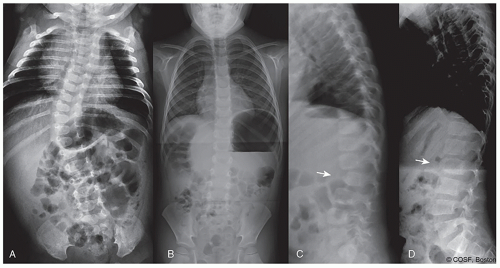

The rate and timing of progression vary widely in pediatric spine deformity with differing diagnoses and ages. Accurately predicting the future of a deformity with a particular diagnosis is challenging, but made more likely by a thorough knowledge of the natural history of that particular diagnosis. For example, spontaneous improvement is likely in infantile idiopathic scoliosis (IIS) with a low rib-vertebral angle difference (RVAD) or in developmental thoracolumbar kyphosis (Figure 1.2), while progression of a dysplastic kyphoscoliosis in neurofibromatosis in the preadolescent growth spurt is inevitable. Many congenital deformities progress during rapid growth in the first 3 years of life, remain stable through the remainder of childhood, and then progress again with the early adolescent growth spurt (Figure 1.1). Knowledge of these diagnosis-specific natural histories permits accurate timing of intervention and avoids unnecessary treatment. Deformity behavior after growth is similarly dependent upon underlying diagnosis. Localized congenital deformity within the thorax likely remains stable after growth in spite of a large Cobb angle, while a thoracolumbar curve with a lesser magnitude in a connective tissue disorder will steadily progress after growth. Neuromuscular patients with poor core muscle strength may likewise progress steadily after maturity. Measuring deformity Cobb angle is an incomplete predictor in pediatric spine deformity. Only by knowing the natural history of the individual diagnosis can we make appropriate surgical choices.